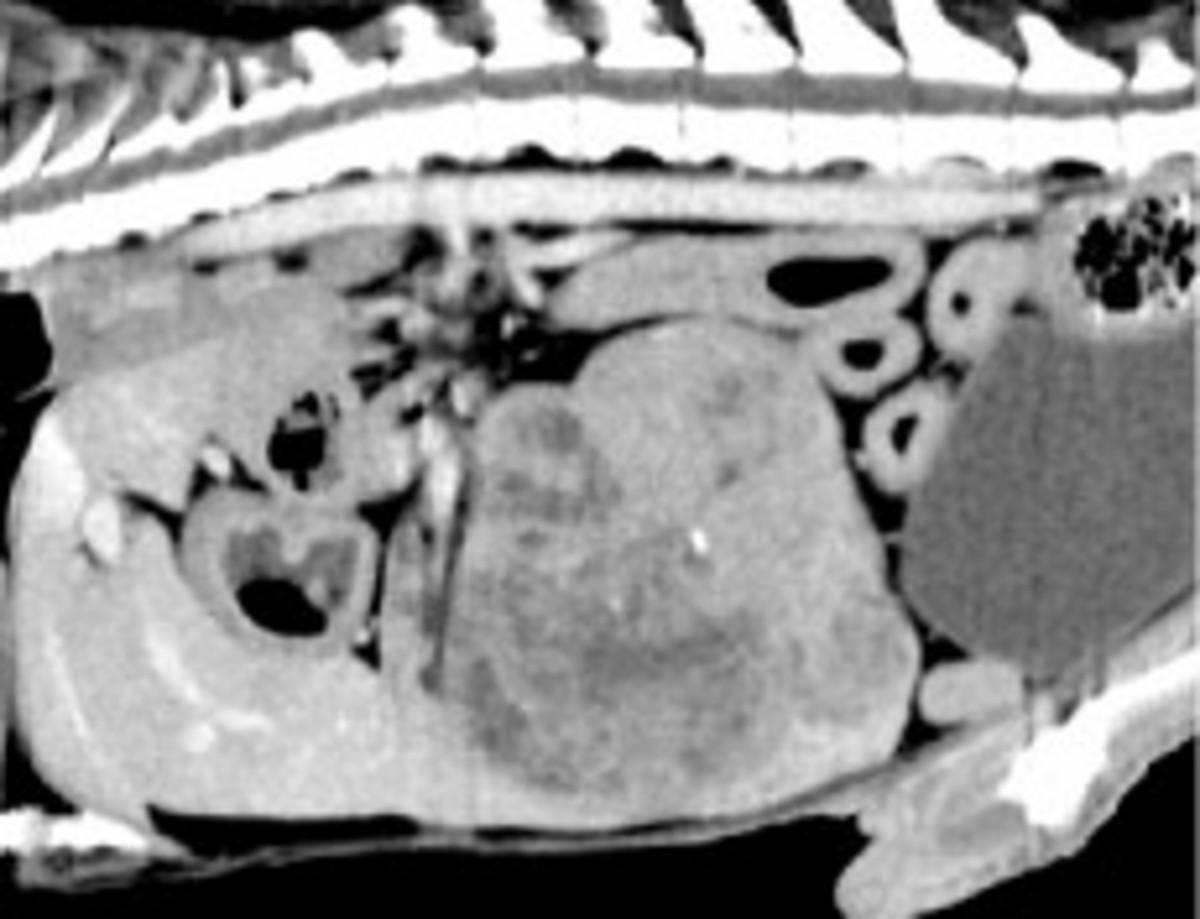

ヨークシャーテリア、未去勢雄、12歳、体重3.4 kg(BCS3/5)です(図8)。両眼の羞明を主訴に近医を受診し、その時の検査にて肝臓に腫瘤が見つかったため、肝臓腫瘤に対する精査および治療を求めて紹介受診しました。初診時の血液検査では、低血糖およびGPTの上昇が認められました(表3)。X線検査および超音波検査にて肝右葉に腫瘤が認められたため(図9)、CT検査を実施しました。CT検査では肝右葉から突出し、周囲肝組織と比較して低吸収を示す腫瘤(6.0×6.0×7.9 cm)が孤立性に認められました(図10)。これら検査所見や造影剤による染色性から肝右葉に主座する孤立性の肝細胞癌が疑われました。また、肝腫瘍以外に低血糖の原因となる異常が認められなかったため、低血糖は腫瘍随伴症候群であることが疑われました。肝腫瘤は外科的に完全切除が可能と考えられたため、開腹下で切除する計画としました。周術期の血糖管理については、先の門脈体循環シャントの症例とほぼ同様に計画しましたが、本症例では腫瘍切除後、腫瘍からのインスリン様成長因子の分泌がなくなることから、高血糖になることが想定されましたので、腫瘍切除後は血糖値をモニターしながらグルコースの輸液を減じることを予定しました。

図10 造影CT検査 矢状断像